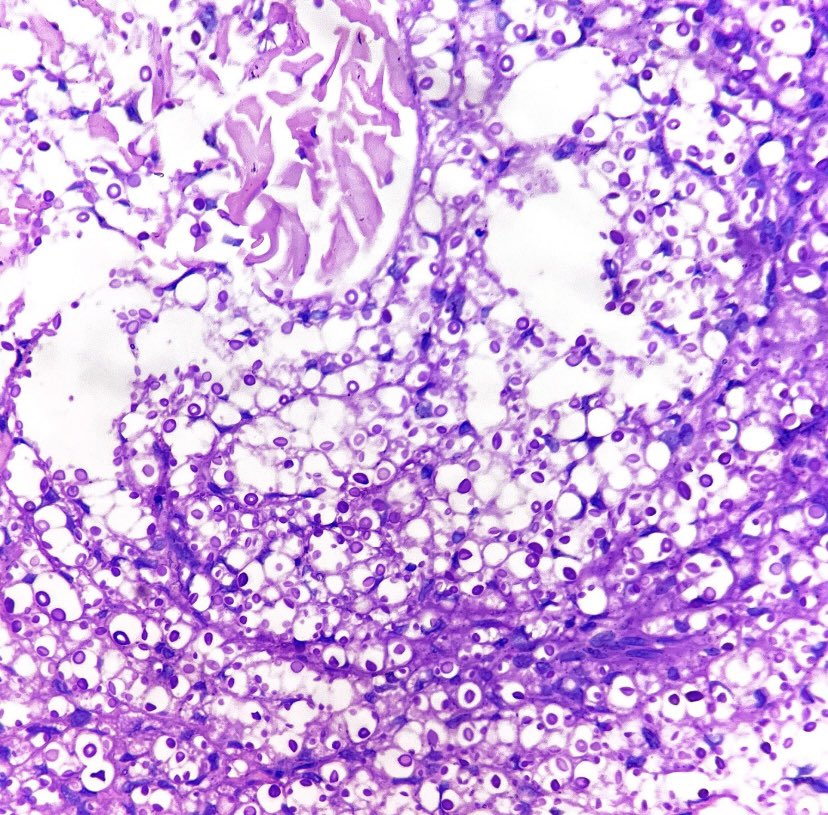

Very nice article by Jerad Gardner, MD and Sara Shalin - Dr. Selim spoke on this at #ASDP21 #dermpath #pathology #dermatology